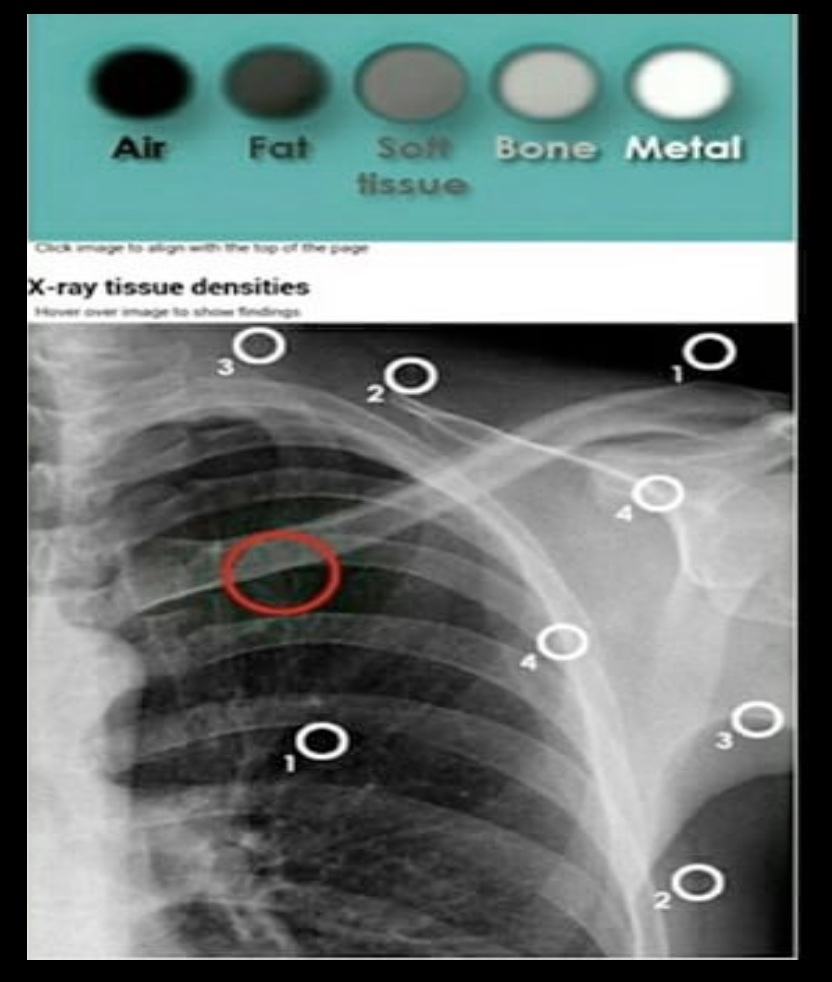

Densidades básicas en rx

• Metal / Hueso compacto = Densidad más alta

• Músculo / órganos sólidos

• Agua/= Densidad intermedia

• Grasa

• Aire/Gas= Densidad más baia